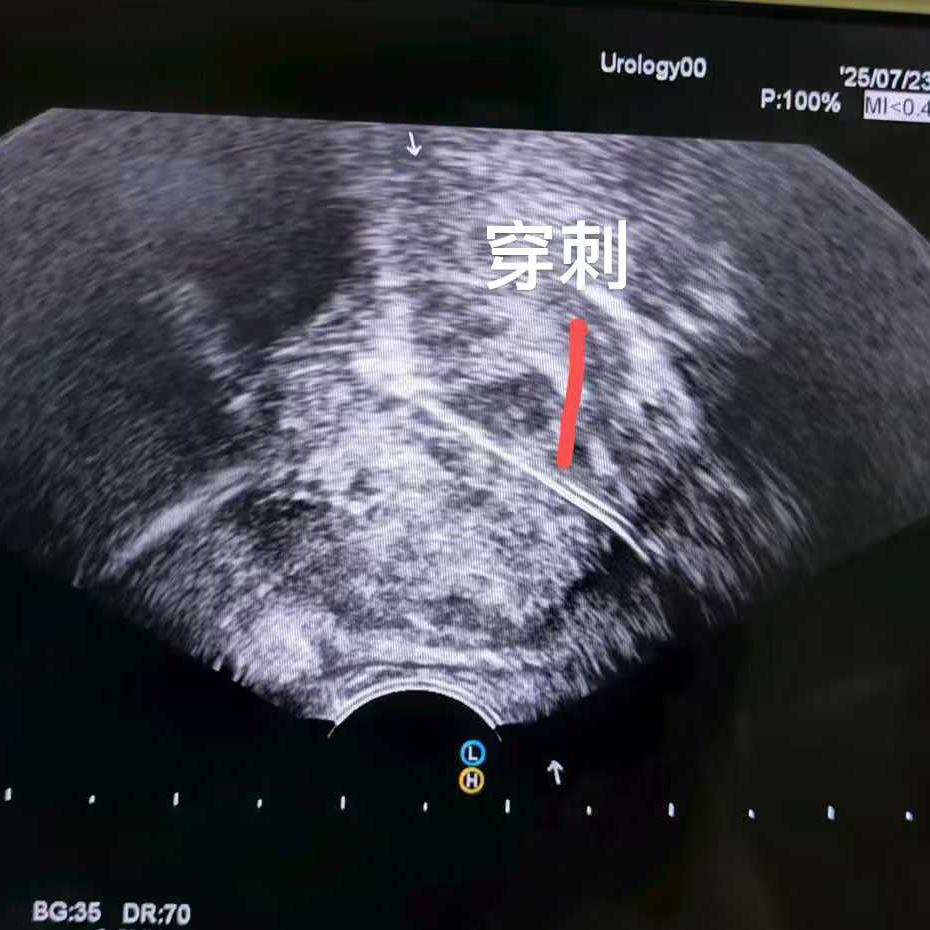

比如這位馬來西亞患者,PSA指標正常,但影像卻發(fā)現(xiàn)可疑病灶,結(jié)果穿刺證實是少見的前列腺尿路上皮癌,在我院接受了冷凍消融治療。

換句話而言,PSA能夠很好地預測前列腺癌的可能性,但是畢竟不是金標準。確診前列腺癌必須輔以病理診斷。

這也讓多數(shù)患者提出疑問:我復查PSA都正常了,為什么還要做穿刺?這里給大家分享我國《中國臨床腫瘤學會(CSCO)前列腺癌診療指南2025》中推薦的前列腺初次穿刺指征: